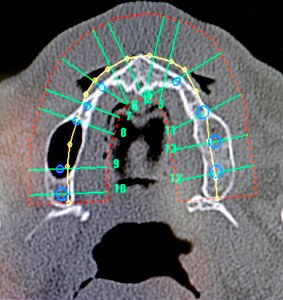

Das 3-D Modell kann virtuell gedreht und gewendet werdenAblauf während der OP Ein optischer Sensor vermisst hochpräzise die Lage von Patient und Bohreinheit. Das Navigationssystem zeigt dem Operateur über intuitiv zu erfassende Farbmarkierungen die korrekte Lage seines Bohrers in Bezug auf das zu setzende Zahnimplantat an. Das Verfahren basiert auf Infrarotlicht, das an kleinen, leichten und ergonomisch angebrachten Reflektorkörpern an Bohreinheit und Patient gespiegelt wird. Ähnlich der Wirkungsweise der menschlichen Augen werden die Reflektionsprismen von 2 Infrarotkameras beobachtet und durch Stereovision die räumliche Lage exakt bestimmt. Es befinden sich keine Kabel am Patienten, dadurch wird die Handhabung wesentlich erleichtert. Während der OP wird dem Implantologen die Abweichung zwischen Instrument und geplanter Implantatachse mit einer Genauigkeit im Zehntelmillimeter-Bereich angezeigt und dokumentiert (zur Qualitätssicherung). Das Navigationssystem erkennt automatisch die Länge des eingespannten Bohrers und identifiziert selbständig das gerade zu bohrende Zahnimplantat. Die Tiefe des Bohrers im Knochen kann der Implantologe an einem Rollbalken am Bildschirm verfolgen. Sobald die exakte Tiefe erreicht ist, ertönt zudem ein akustisches Signal. Der Patient wird zur präoperativen Planung im CT-Gerät oder DVT gelagert. Es erfolgt dann ein Spiral –CT des Kiefers mit hochauflösenden dünnen Schichten. Die gesamte Untersuchung der Radiologen in Berlin dauert einschließlich Lagerung für den Patienten ca. 2 bis 3 Minuten. Der Datensatz des Kiefers wird dann mit den Rekonstruktionsparametern weiterverarbeitet. Diese Information wird einer CD-ROM für den Patienten gespeichert und steht dann für den Operateur zur Verfügung.